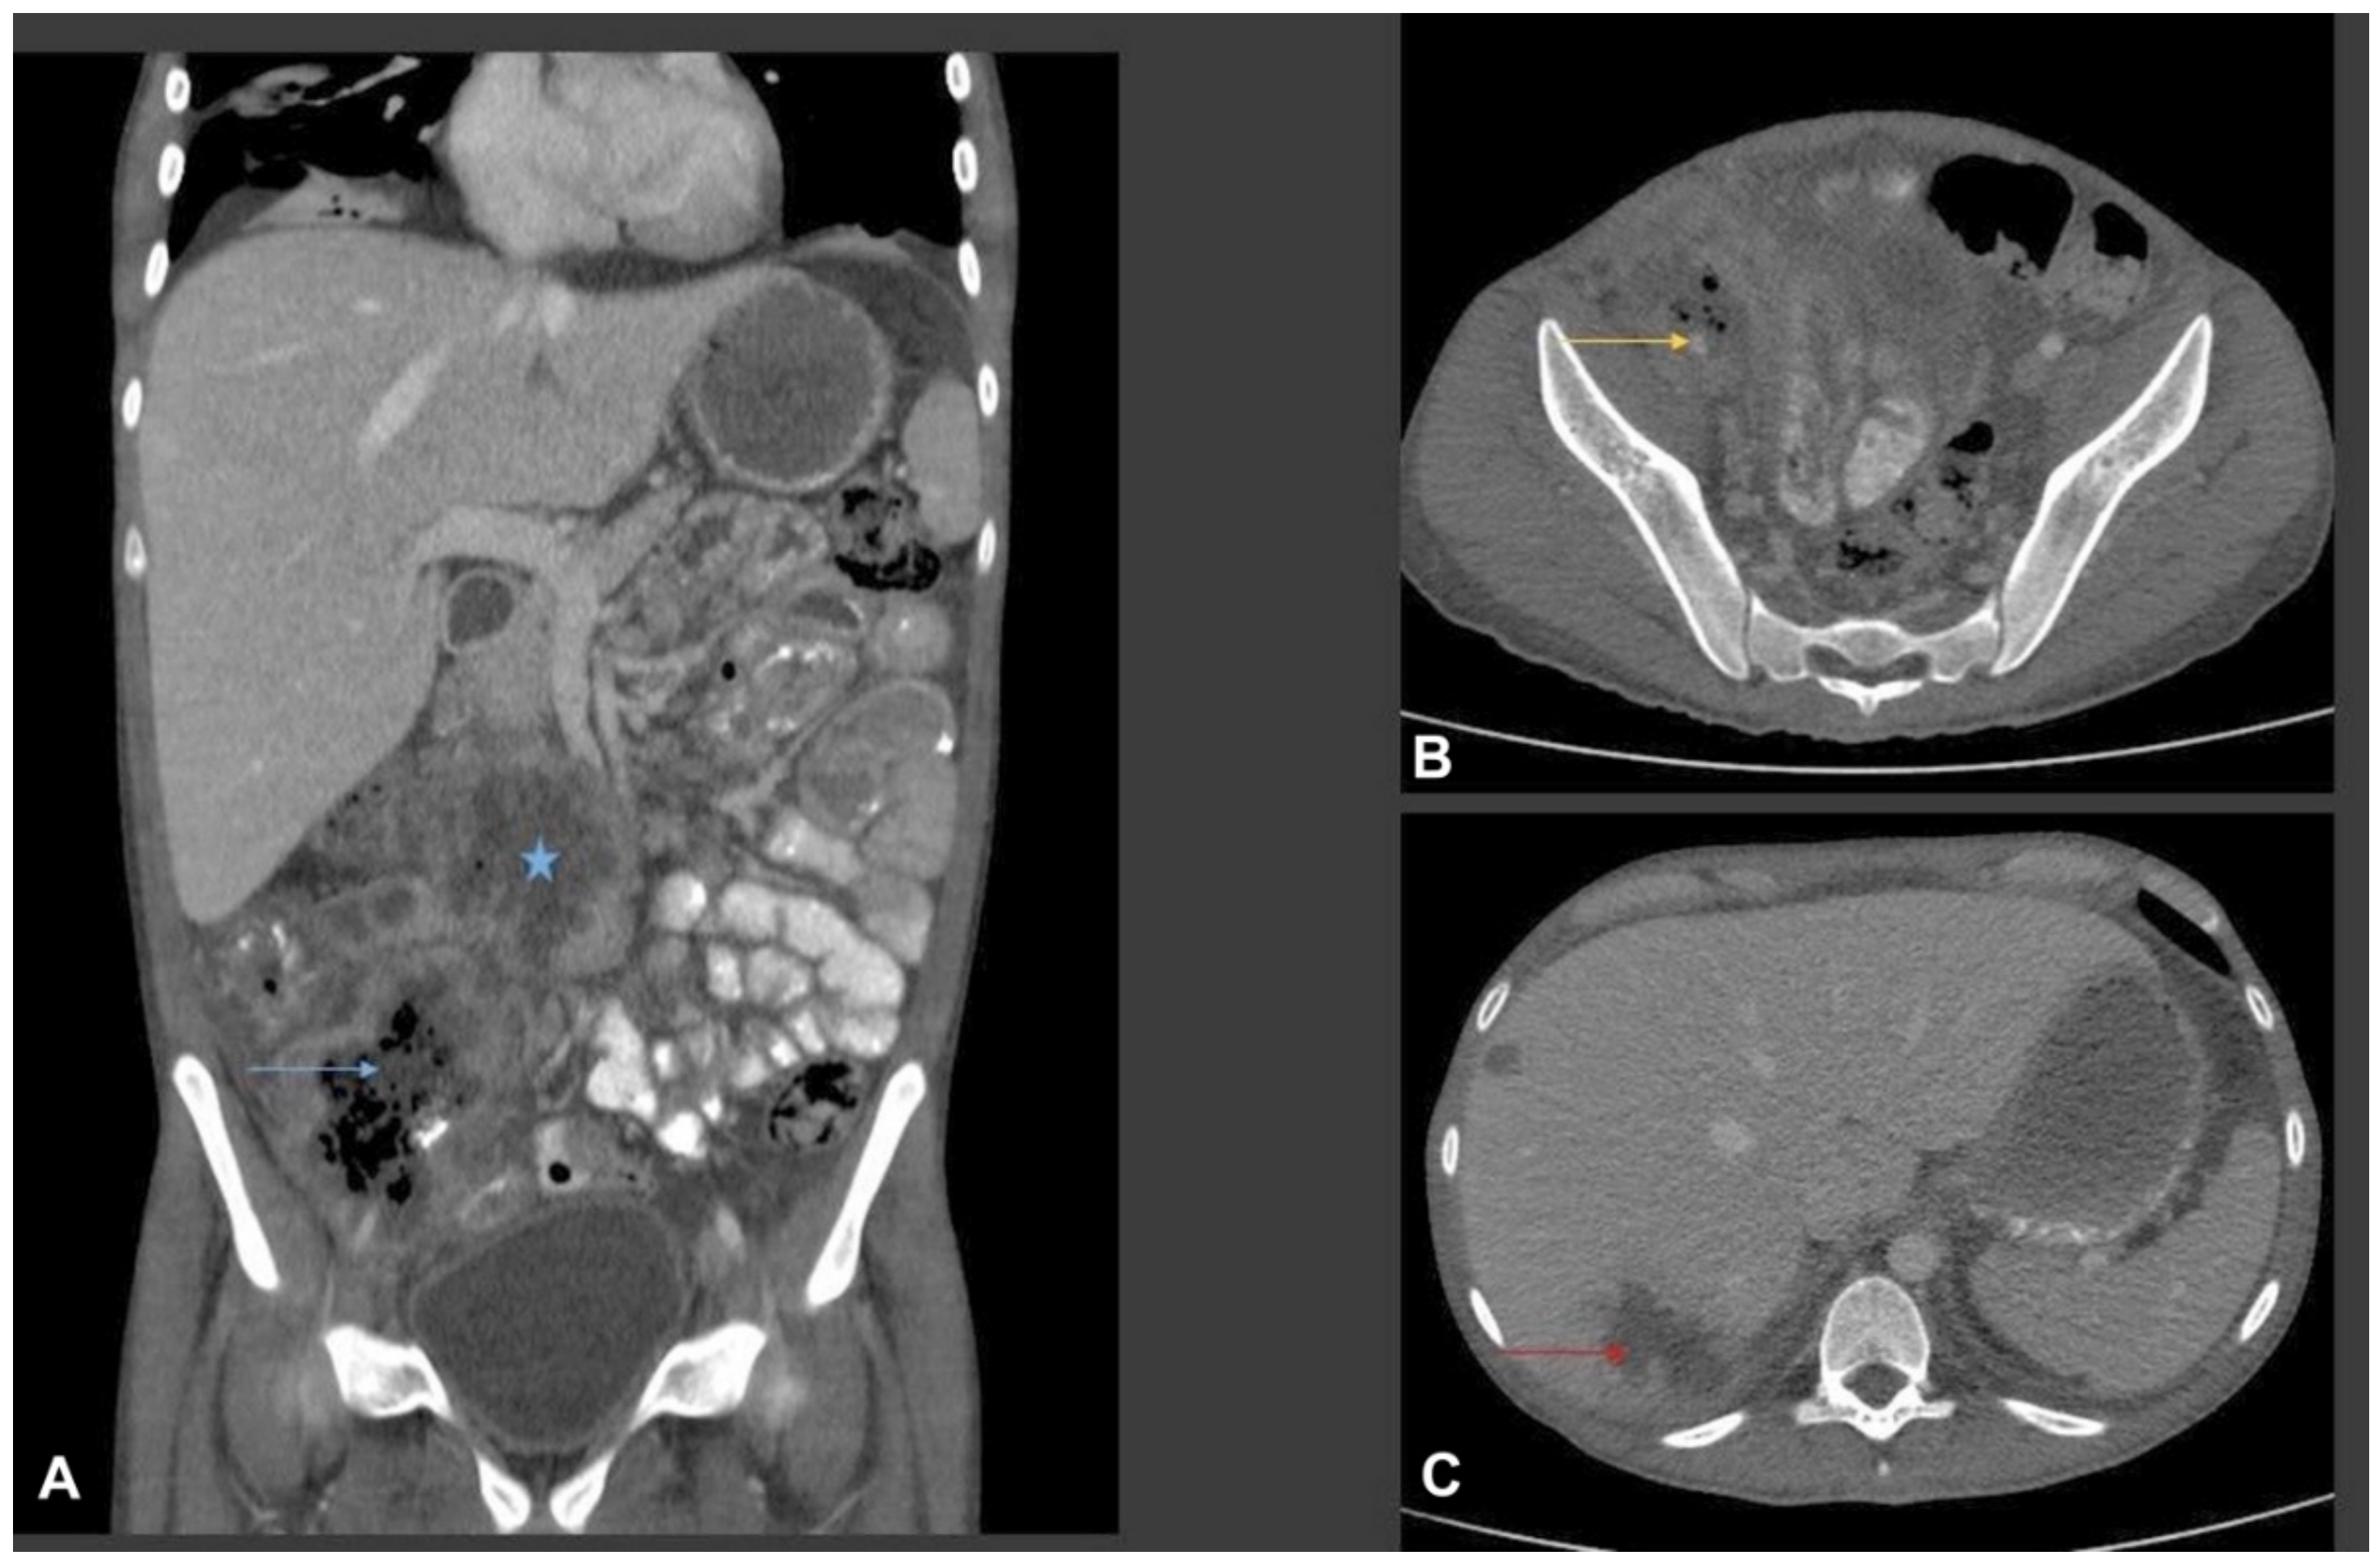

The patient underwent urgent right common femoral artery thrombectomy and embolectomy. Multiplanar CT scan of abdomen and pelvis were performed with oral and intravenous contrast (Figure 1).

Figure 1.

Multiplanar CT scan of abdomen with oral and intravenous contrast. (A) Coronal CT image shows a multispatial ill-defined low-attenuation ring enhancing collection in the root of the mesentery (star) and in the right iliac fossa. The right iliac fossa collection shows thick irregular rim enhancement with central bubbly air lucency (blue arrow). Bowel loops are adherent to the collections. There is marked inflammatory fat stranding noted in the right iliac fossa and right side of the pelvic cavity. Small volume ascites. (B) Axial CT image from the right iliac fossa and pelvis shows marked phlegmonous soft tissue lesion with fat stranding. The phlegmonous inflammatory mass is encasing the right external iliac artery which is small and irregular in calibre (yellow arrow). (C) Axial images from the liver show multifocal ill-defined low-attenuation liver lesions of variable size (two of them shown in this image). The largest was seen in the subcapsular liver in the segment VII and shows surround oedema, suggestive of liver abscess (red arrow).

We report a newly described Basidiobolus species causing refractory angioinvasive gastrointestinal disease (GIB) in a 20-year-old Omani patient with type 1 diabetes mellitus. His disease seemed to have started in the caecum with extension to the major vessels of the lower limbs. Physical examination of the lower limbs demonstrated signs of acute ischemia, confirmed by imaging studies including CT (Figure 1, Figure 4 and Figure 5) and by histopathology (Figure 3). From a clinical perspective, the present case is similar in main traits to other reported cases of GIB. The infection is a rare but possibly emerging disease entity, affecting immunocompetent individuals including children, and mainly occurs in hot climates worldwide [35]. In many earlier reported cases, surgery was performed without preceding diagnosis of GIB [36].

Laboratory results of our patient show an elevated white blood cells count (WBCs) of 16,700 cells/µL, with an elevated eosinophil count of 1000 cells/µL, normal glycosylated haemoglobin and deranged liver function tests. These results agreed with previously reported cases where elevated WBCs and eosinophilia were observed [37]. Abdominal imaging studies such as computed tomography (CT) are often used during the evaluation of patients with GIB [37]. In a review of abdominal imaging findings in GIB, Flicek et al. [41] commonly found abdominal masses in colon, liver or multiple sites, and bowel wall thickening. Although such findings are not diagnostic of GIB, the authors concluded that in the right clinical and epidemiological context, one should suspect GIB when an abdominal mass is seen upon CT scan [41]. In our patient, abdominal CT scans revealed a complex caecal mass adherent to the pelvic floor and to the terminal ileum with multiple hepatic lesions (Figure 1). Histological criteria such as a granulomatous reaction and mycological evidence of fungal structures are taken as suggestive of GIB [42,43]. Detailed examination of the thrombus and a section of the small intestine of our patient showed thin-walled, broad and septate hyphae, and these features are compatible with zygomycete-like fungi (Figure 3). Diagnosis of Basidiobolus infection down to the species level is typically accomplished by microbiological culture as gold standard [44]. From the thrombus specimen that was extracted from the common femoral artery, and from a urine sample, a mould was grown reminiscent of a Basidiobolus species. The colonies on PDA were expanding, subhyaline, waxy and without aerial mycelium. The wet mount preparation showed morphological characteristics consistent with Basidiobolus by production of zygospores with smooth walls, and retained short, paired protuberances leading to a structure known as “beaked zygospore”. In addition, apical, globose primary conidia were produced with forcible conidium discharge from the conidiophores, and with pyriform secondary conidia (Figure 2 and Figure 7). The thin ballistoconidia were seen only in the primary culture (Figure 2F). Overall, distinct morphological traits are minimal or absent between Basidiobolus species. Most of the Basidiobolus species had been distinguished on the basis of phenotypic differences such as the form of zygospores, formation of aerial hyphae, production of exogenous microspores and odour production during growth, as well as growth temperature preferences [18].